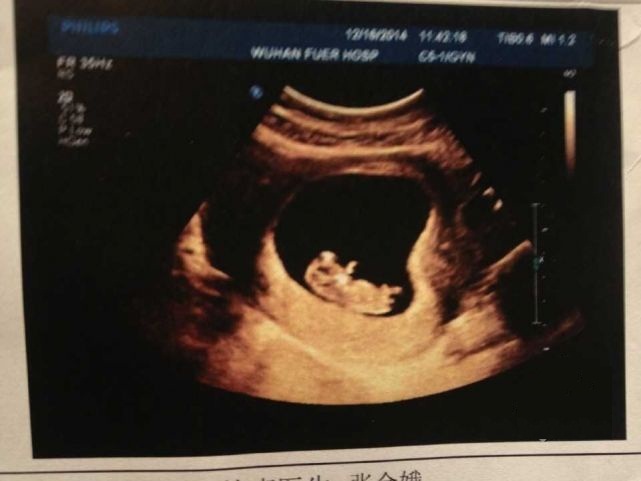

怀孕10周去照B超,第一次真切的看到宝宝,胎心胎芽都有了,小手小脚真的好可爱,我忍不住红了眼眶,再剧烈的呕吐我也要克服,要为宝宝变得更坚强!